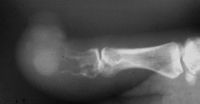

This elderly gentleman presented with an enlaging

tumor of his thumb tip. He did not know how long

it had been present. He complained that it bled

frequently, was unstable, and he requested an

amputation. He had no lymphadenopathy or evidence of

metastatic disease on chest Xray. |

| Plain films showed

loss of the distal 2/3 of the distal phalanx. |